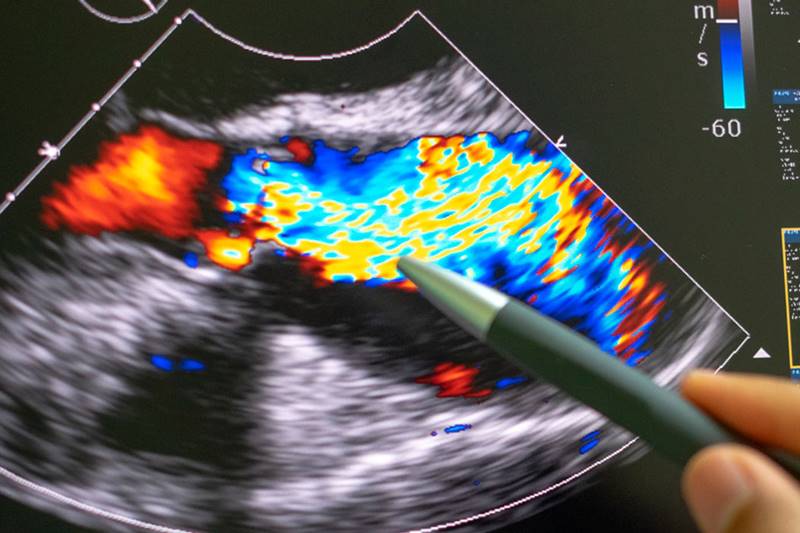

A princípio o CES funcionará aos sábados apenas para realização de ultrassonografias já agendadas pelo sistema através das Unidades Básicas de Saúde. Ao todo serão 24 exames por semana, sendo 12 às quartas-feiras e 12 aos sábados.

A iniciativa do prefeito Mão Santa, garantirá maior agilidade e redução do tempo de espera para a realização de exames solicitados por profissionais de saúde do município. Confira os exames de ultrassom disponíveis na unidade: